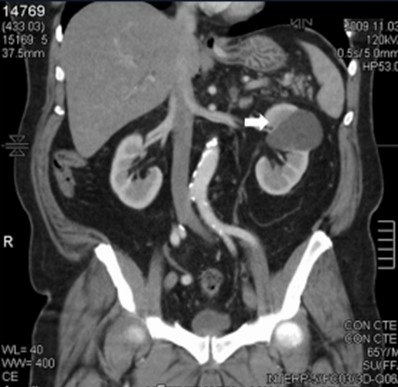

La Categoría IIF exhibe múltiples septos finos en su interior, realce evidente en paredes o septos, mínimo grado de engrosamiento de la pared, calcificación grosera o nodular, lesiones intra renales densas sin realce o con realce de septos o pared, siendo este realce no medible en las lesiones descubiertas con incremento de la densidad radiológica cuando se comparan las imágenes sin y con contraste yodado IV. Se consideran masas quísticas moderadamente complicadas y precisan seguimiento con controles cada seis meses.(19, 20) No requieren tratamiento quirúrgico inmediato y el riesgo de evolucionar a quistes malignos es del 5%, quistes con aspecto hiperdenso > 3 cm (Anexos 7 y 8).

La Categoría III muestra engrosamientos lisos o irregulares de la pared o de los septos intra quísticos y existencia de realce medible en TC y RMI. Se consideran masas indeterminadas y precisan de primera instancia cirugía, nefrectomía parcial o ablación por radiofrecuencia, salvo contraindicaciones clínicas.(19, 21) Aproximadamente el 40%-60% son lesiones malignas (carcinomas renal quístico), siendo el restante benignas, que incluyen quistes hemorrágicos, infectados crónicos o calcificaciones parietales, nefrona quístico multiloculado, quistes multilobulados, quistes con tabiques complejos, etc. (Anexos 9 y 10).

La Categoría IV presenta captación de un componente sólido intra quístico, muestra realces nodulares fuera de la pared y de los septos interpuestos en el área quística compleja, calcificaciones gruesas, vascularizadas con un importante realce con contraste yodado IV. En realidad, son lesiones malignas con componente quístico. Se trata de neoplasias quísticas, y precisan cirugía y estadificación.(19, 21) (Anexos 11 y 12).

- Bosniak IIF: en esta categoría, el 4% de los quistes (20 pacientes) presentaron complicaciones. De estos, el 70% (14 pacientes) presentaron quistes hemorrágicos, mientras que los restantes presentaron calcificaciones parietales. En un caso (2% de esta categoría) se observó evolución hacia malignidad, con realce en la TC (Anexo 21).

- Bosniak III: el 3% de los quistes (15 pacientes) fueron clasificados como Bosniak III, con 11 pacientes de sexo masculino y 4 de sexo femenino (Anexo 22).

- Bosniak IV: finalmente, el 3% de los quistes (15 pacientes) fueron clasificados como Bosniak IV, de los cuales 12 pacientes eran de sexo masculino y 3 de sexo femenino. Estos quistes presentaron características de neoplasia quística renal y carcinoma renal quístico, lo que requirió intervención quirúrgica inmediata (Anexo 23).